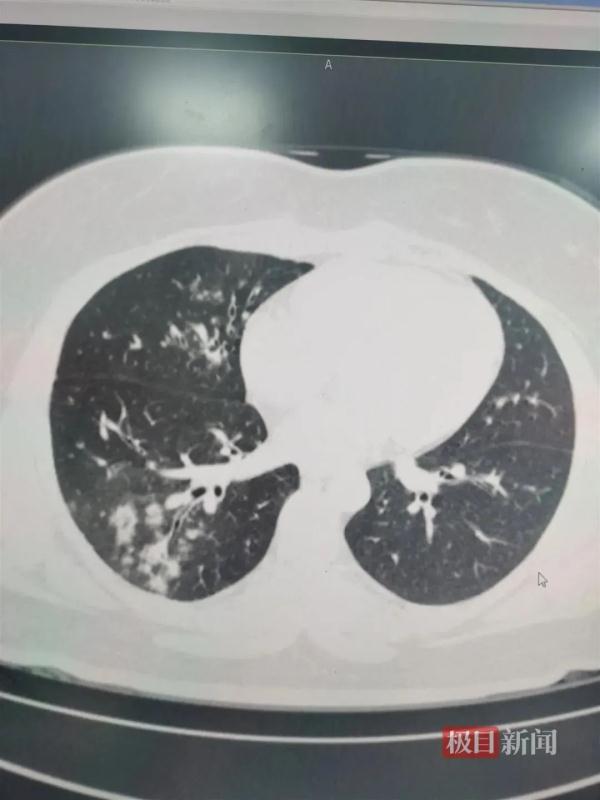

△支原体感染患者肺上呈现树雾状。

这是因为,肺炎支原体会在人体内激发出人体的免疫反应。从患者胸片,可以看到范围大小不等“白肺”的地方。

这不是说那里全是“支原体”,而主要是支原体激发出的免疫损伤、炎症浸润。

可以说,支原体肺炎是感染+免疫反应引起的肺炎。